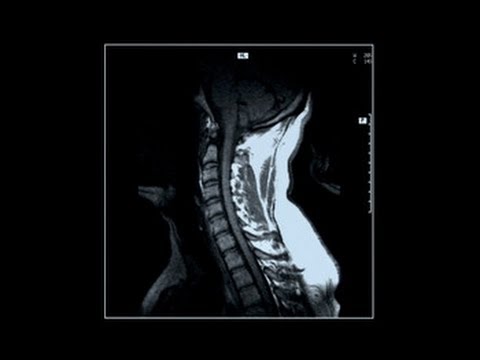

Print Version Kyphosis Introduction. The spine is divided into three sections: the cervical spine or neck, the thoracic spine or mid back, and the lumbar spine or low